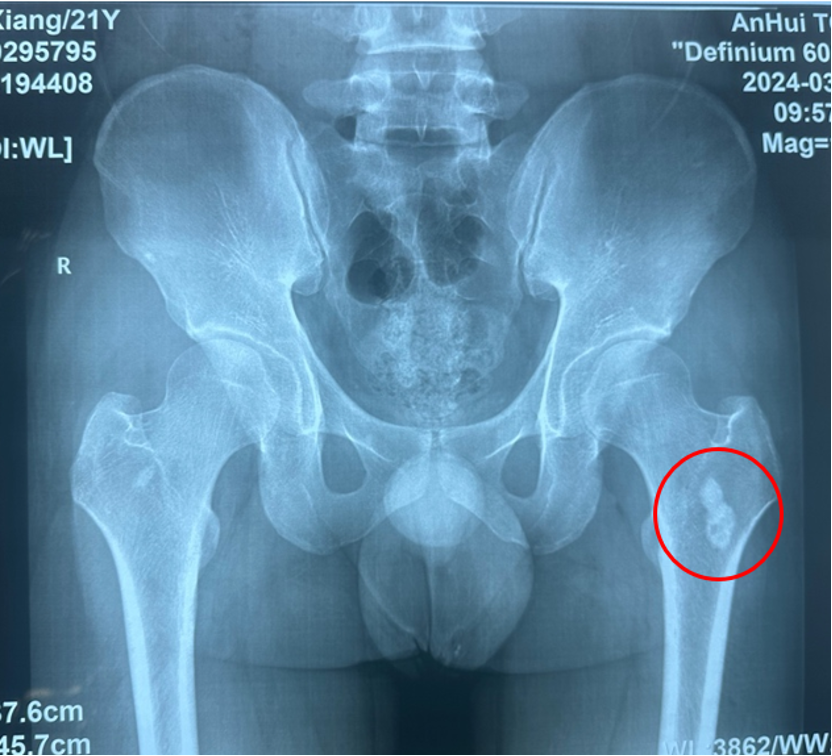

患儿,12岁,活泼好动的男孩,因"左大腿疼痛2个月,加重伴肿胀1周"来我院就诊。起初家长以为只是生长痛或运动损伤,直到疼痛日益加重并出现局部肿胀才引起重视。